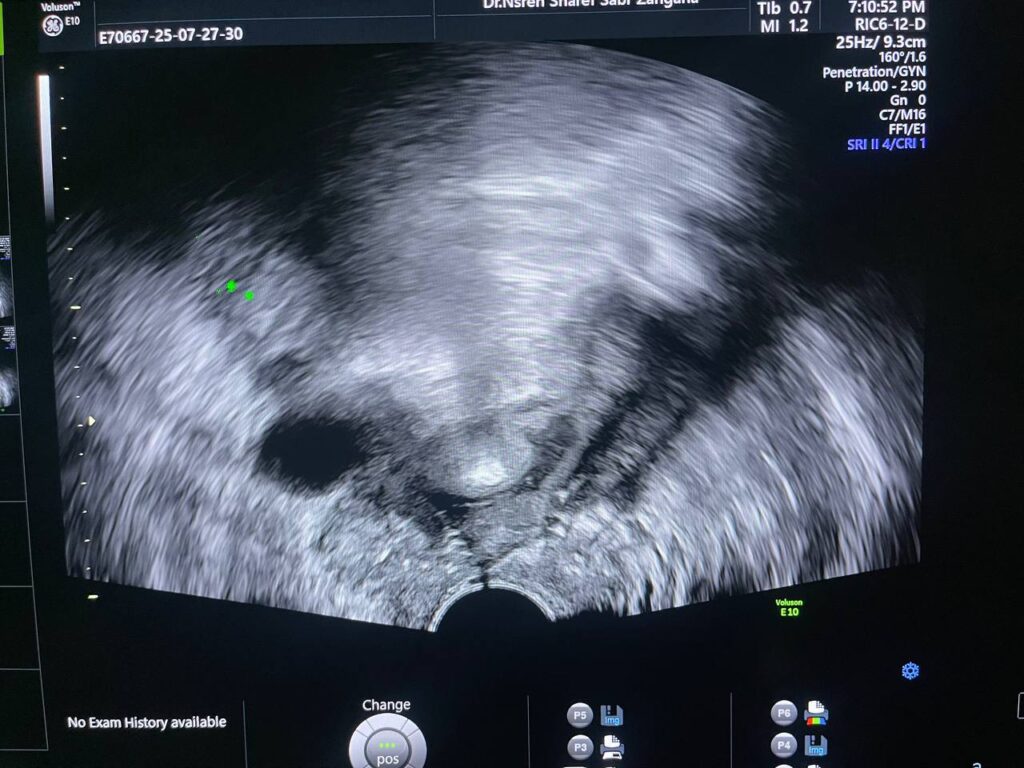

Post Hystercetomy Abcess Formation

Uterus removed , with presence of collected heterogenous fluid 27x14mm in the bed , contain air , could be abscess ? please for further study to exclude other pathology